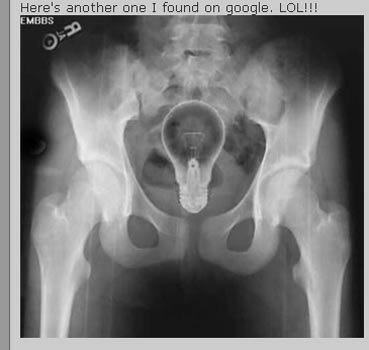

Trong trường hợp này thì sáng kiến nhét bóng đèn vào người lại là một tối kiến.